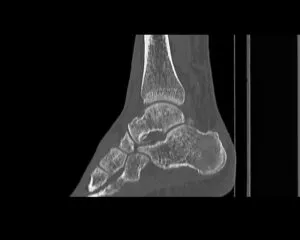

CT

GE社製Revolution ACT(16列)を導入しています。X線を利用して体の断面(輪切り)を撮像する検査です。この輪切りの画像をコンピューターで処理することにより、様々な方向からの断面像や3D画像を得ることができます。

CTで検査した画像